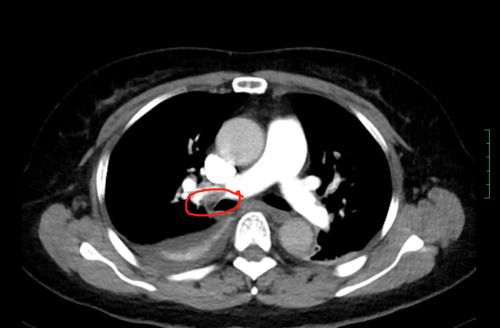

ct上可以看到,患者双侧肺动脉均有血栓形成。

情况十万火急,尹新民主任边现场组织抢救,边将情况汇报给向华副院长,向华副院长立即调度全院各相关科室予以协助。一场与生命的赛跑由此拉开!超声科紧急为患者进行床旁彩超,找到肺动脉栓塞的“罪魁祸首”为左下肢静脉血栓。在呼吸治疗组的协助下,医护人员携带转运呼吸机快速运送方女士至介入手术室。介入血管外科紧急安排了手术医生和手术间,由张永琎副主任医师等为患者施行“肺部血管造影”,明确诊断为双肺动脉急性栓塞,随即为其实施“双肺动脉尿激酶冲击溶栓、下腔静脉滤器植入术”。术后,患者肺动脉供血明显改善,血氧饱和度立即回升,被送往重症医学一科继续治疗。